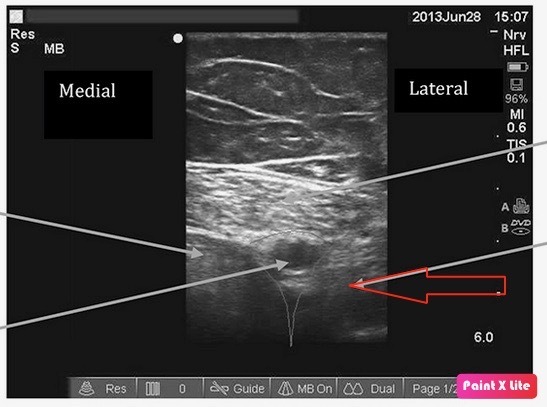

Q5: Anatomy of the adductor canal

You are performing a regional block for analgesia following knee surgery. You have an ultrasound probe scanning the anterior mid-thigh. The muscle indicated by the arrow in the ultrasound image below is the

A: Sartorius

B: Vastus Medialis

C: Adductor Longus

D: Gracilis

E: Rectus femoris

A

Answer B Vastus Medialis